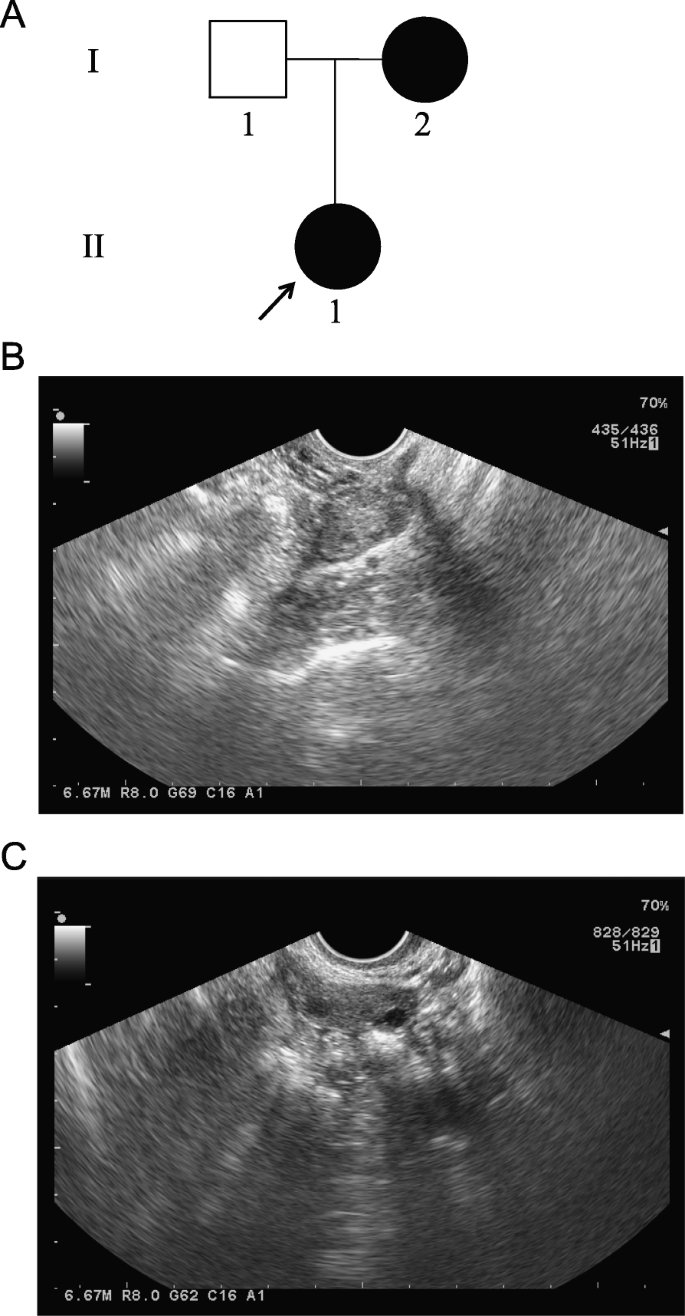

All procedures involving human participants were performed in accordance with the ethical standards of the Ethics Committee of the First Hospital of Shijiazhuang and the 1964 Helsinki declaration and its later amendments. Written informed consent was obtained from each participant. The proband (Fig. 1a, II-1) with DOR was recruited from the First Hospital of Shijiazhuang. The proband developed DOR in 2018 at the age of 28. The hormone levels of the proband were as follows: follicle-stimulating hormone, 8.71 IU/L; luteinizing hormone, 2.93 IU/L; estradiol, 62 pmol/L; testosterone, 0.48 nmol/L; prolactin, 8.32 ng/mL; and anti-Mullerian hormone, 1.67 ng/mL. Ultrasound imaging of the left (Fig. 1b) and right (Fig. 1c) ovaries showed no antral follicles and one antral follicle, respectively. In addition, the proband’s mother (Fig. 1a, I-2) developed amenorrhea at the age of 39.